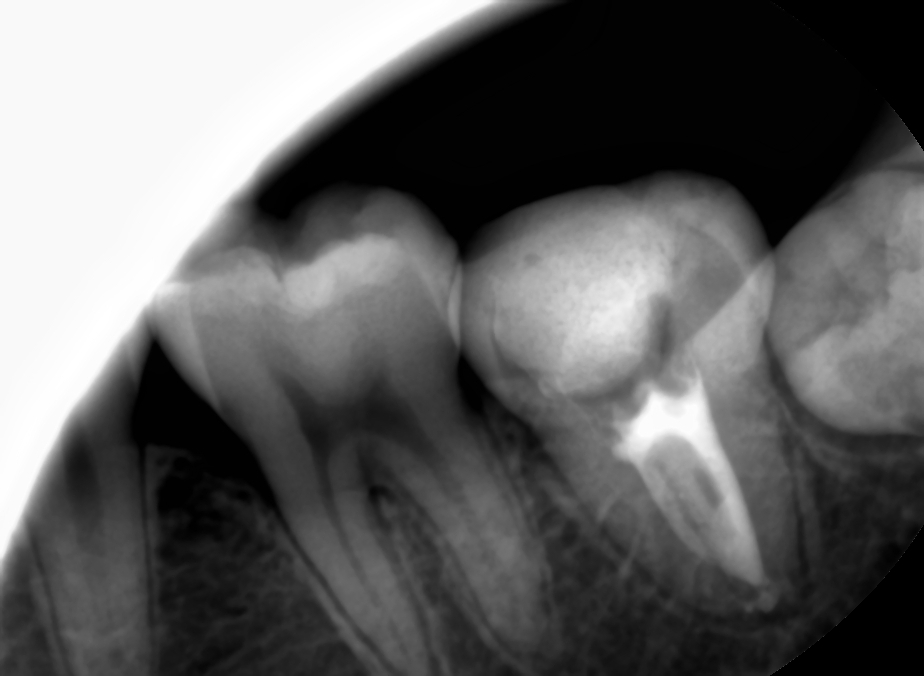

좌) 저번주 첫 필링 당시 사진 / 우) 이번주 다시 필링

보다시피 처참하게 언더필링이 돼서 진짜 깜짝 놀랐다. 아니 왜 저 자리에서 0.5사인이 나는 거지? root ZX만 믿었다가는 이렇게 되는구나. 그러니까 아파하시지🤦♂️ 필링 후에 다른 체어 진료 계속 뛰다가 뒤늦게 필링 사진 열어보고서는 진짜 깜짝 놀랐었다. 그래도 차트에 내가 WLD다시하고 CF도 다시 한다고 적어놨었고 목요일에 마침 오셔서 GP 다 긁어내고 세척 소독 한 다음 이번엔 제대로 워킹랭쓰 재고(근데 이번에도 저 위치에서 또 0.5사인 뜨더라.. 무시하고 더 집어 넣으니까 신호가 죽었다가 다시 살아남;;) 필링 해냈다. 휴~

근데 이거는 root ZX로 잰 워킹랭쓰까지 다 넣었는데 언더난 거고, CF날 임시가봉제 제거하고 GP콘 넣어보면 저번에 잰 워킹랭쓰까지 잘 안들어가는 경우가 많은데, 그런 경우 보통 원장님들께서는 Gp콘 사이즈 오차를 많이 말씀하시지만 초보자에게 더 흔한 오류는 ①WLD할 때 reference point를 일정하게 잡지 않고 이상한데다 잡았거나(straight line access 문제), ②근관의 taper와 GP콘 taper가 서로 안맞거나(이때는 taper 큰 파일로 훑어주거나, 아니면 circumferential filing을 해주면 들어간다)인 경우도 많은 것 같다. 진짜 드물게 임시가봉할 때 넣어놨던 cotton pellet이 MAF확인한다고 핸드파일 집어 넣다가 근관 끝까지 다져넣어 끼일 수도 있다고 한다. 그런 일은 없어야겠지만, 아무튼 워킹랭쓰까지 안들어가면 root ZX를 다시 한 번 써서 확실하게 워킹랭쓰를 다시 잡고 가야하는 게 맞는데.